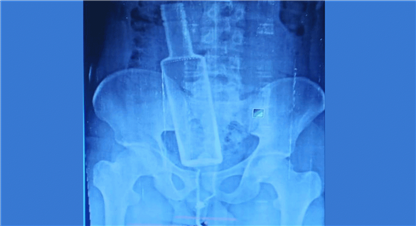

काठमाण्डौं । ऊर्जा, जलस्रोत तथा सिँचाइमन्त्री पम्फा भुसालको मोतीविन्दु (आँखाको नानीमा जालो पर्ने रोग)को सफल शल्यक्रिया गरिएको छ ।

यसै जेठ १८ गते त्रिपुरेश्वरस्थित नेपाल आँखा अस्पतालमा उहाँको दाँहिने आँखाको शल्यक्रिया गरिएको हो । उहाँको शल्यक्रिया आँखा रोग विशेषज्ञ डा. किरण शाक्यले गर्नुभएको हो ।